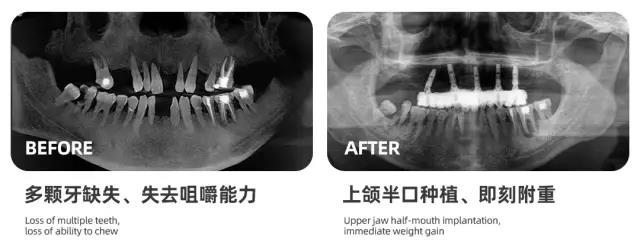

而种植牙是目前最有效的解决缺牙问题的方式,海德堡联合口腔一直致力于通过德国标准的口腔诊疗服务帮助中老年人解决牙齿问题。

通过德国数字化口腔种植技术让更多牙齿缺失的人,在无痛舒适、快速精准的情况下种好牙齿。

在过去的一年,我们已经为天津上万缺牙市民进行了免费口腔检查,同时还为很多缺牙市民完成了种植牙修复,帮助他们彻底摆脱了缺牙吃不好饭、活动假牙不舒服的苦恼。